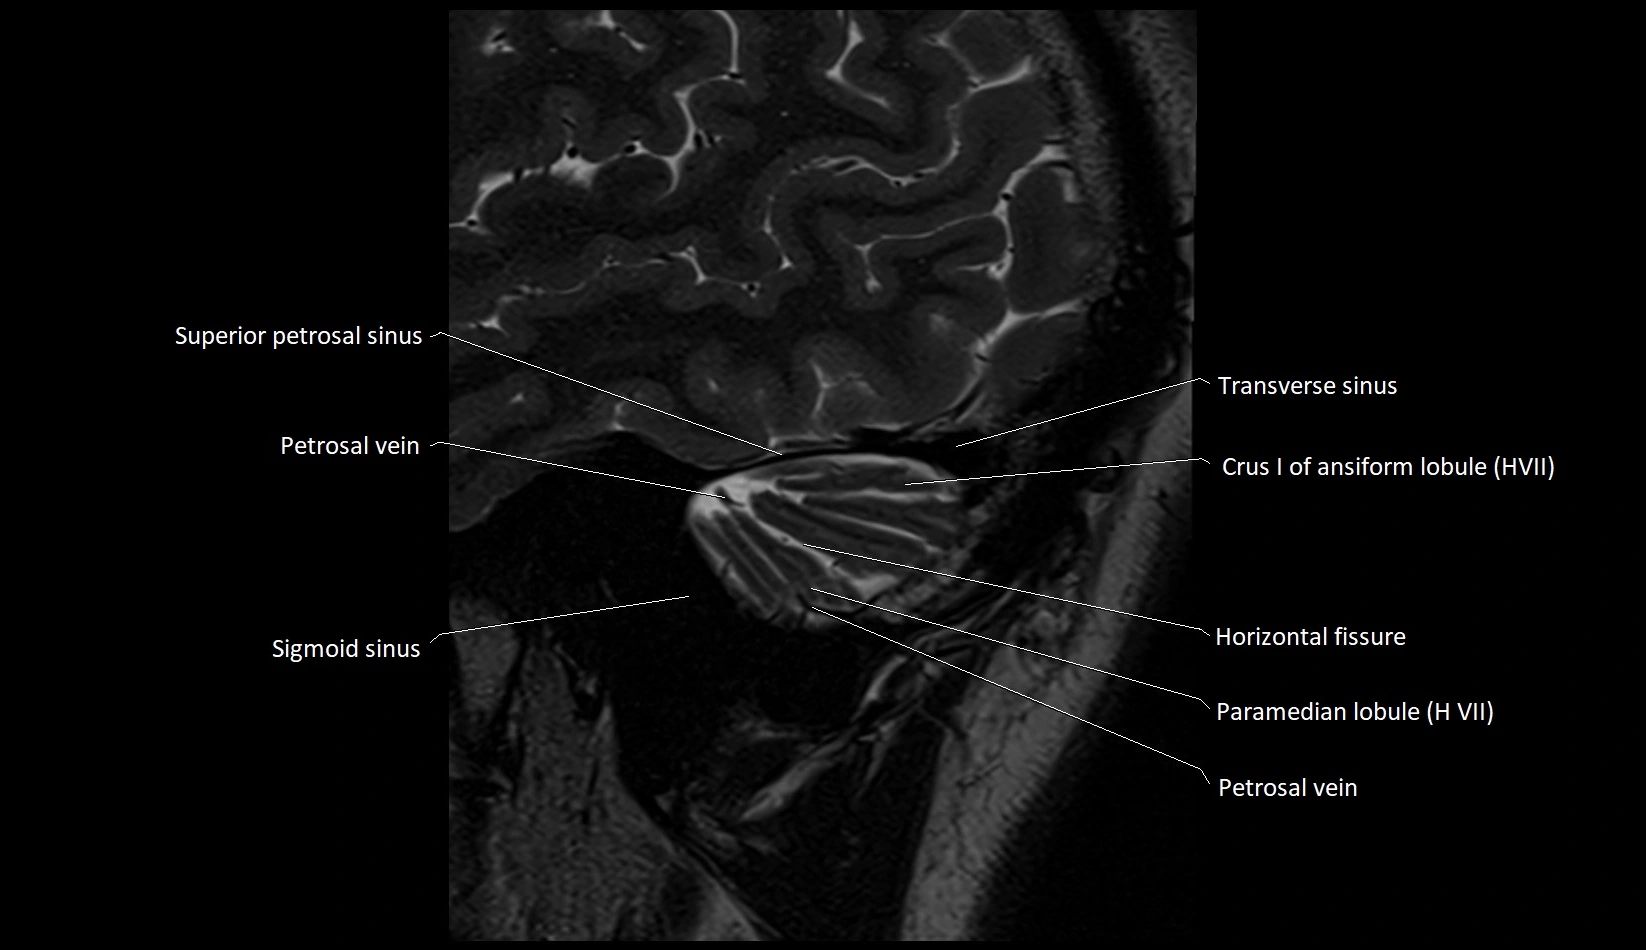

MRI images